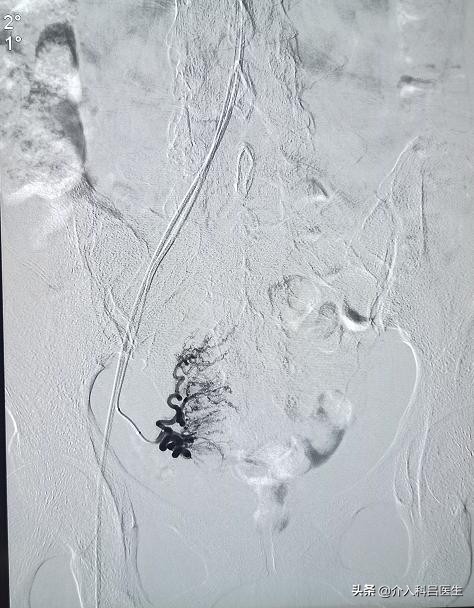

所以说,综合考虑介入栓塞治疗伤口只有一个针管大小,确实让患者少遭了很多罪,我们一直做介入治疗的科普,就是降低患者的创伤,就是前线人率先手术,不破坏前列腺完整,不损害患者的性功能,优势是创伤很小,恢复也快,很多病人术后三天已经完全恢复正常,也没有像电切那样大量出血,不影响生活治疗。

老爷子听完我们的手术原理,接受了介入治疗,住院五天已经自己出院了,身体恢复的很好,他说,没想到困扰十几年的病就这么轻松解决了!